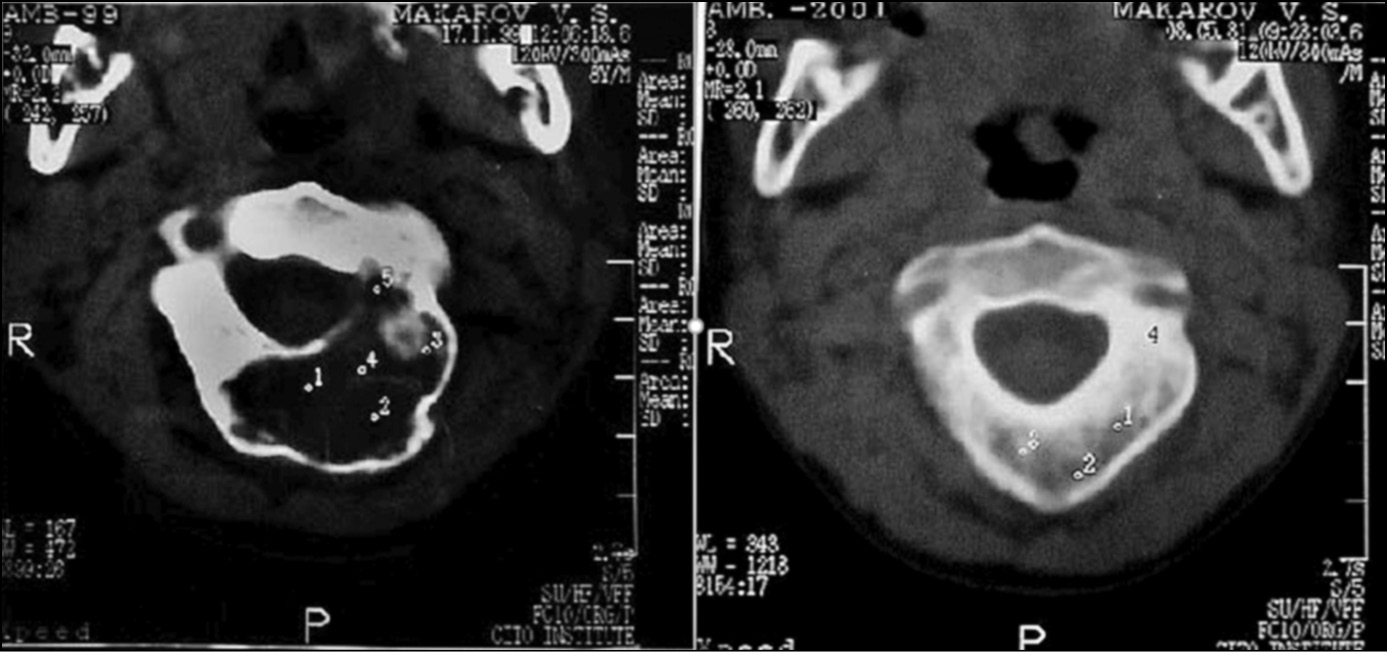

Пункционное лечение аневризмальных кист позволяло снизить риск тяжёлого кровотечения, снизить внутрикистное давление, простимулировать репарацию костной ткани, что снижает интраоперационные риски при открытых операциях, снижает вероятность рецидива, и улучшает послеоперационные результаты. При этом пункцию проводили по возможности не реже чем один раз в 2–3 месяца. Количество пункций составляло от 2 до 6 в зависимости от объёмов патологического очага. Положительная динамик при лечении данной группы пациентов отмечалась не ранее чем через 6 месяцев с момента начала лечения (рис. 2). Критерием положительного результата являлось остановка роста кисты, снижение её активности по сравнению с предыдущими пункциями, формирование зон оссификаци по данным КТ. Оптимальным признаком снижения активности являлось отсутствие активного кровотечения при проведении пункции трепаном.

Рис. 2. Пациент 13 лет. Результат проведения пукционного лечения дуги С2 позвонка через 8 месяцев

Fig. 2. 13-year-old patient. The 8-month result of the injection treatment of C2 arch